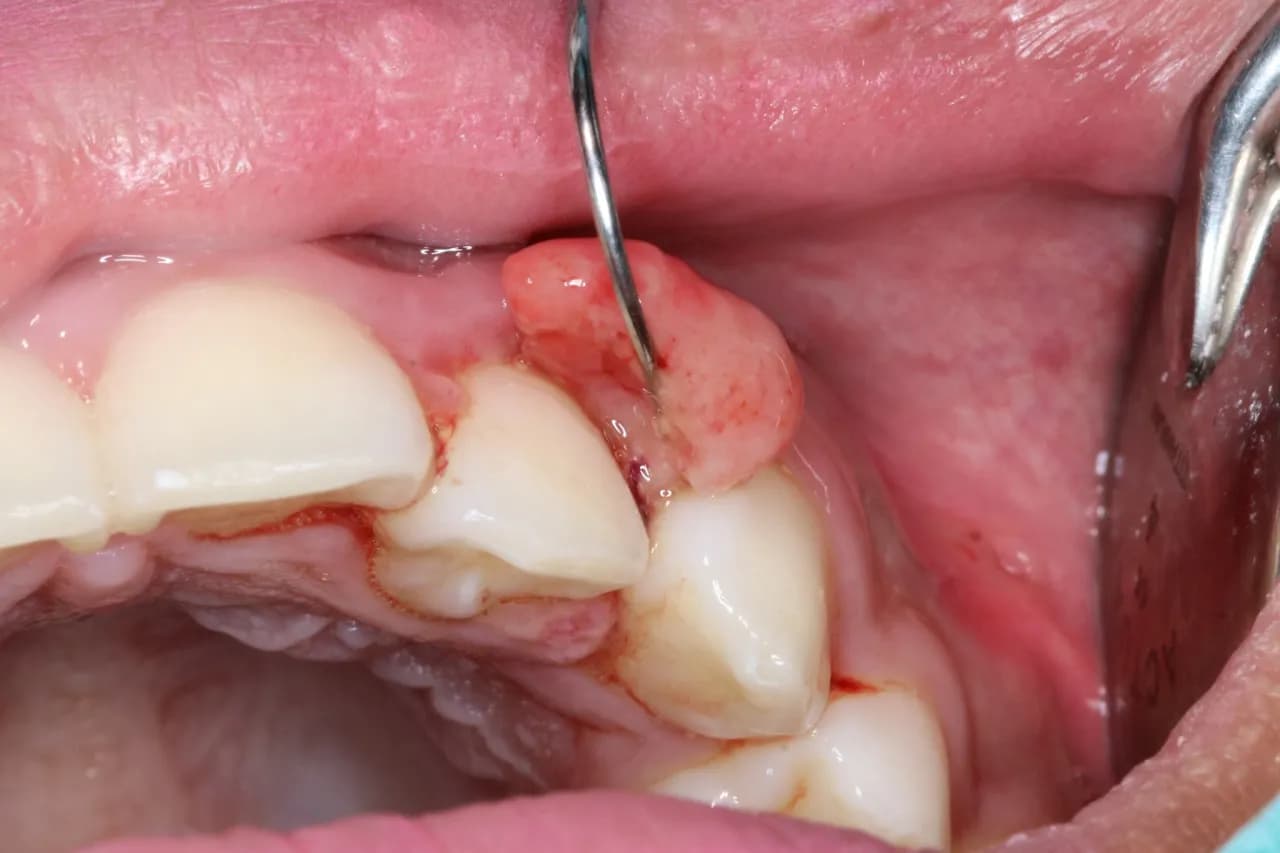

W przypadku raka dziąsła, zmiany wizualne są jednym z pierwszych sygnałów, które mogą wskazywać na problem. Warto zwrócić uwagę na różne cechy, takie jak guzki, zmiany koloru oraz tekstury dziąseł. Zmiany te mogą obejmować twarde guzki o nierównych brzegach, które mogą być bolesne lub krwawić. Dodatkowo, dziąsła mogą wykazywać oznaki zaczerwienienia lub opuchlizny. Wczesne zauważenie tych objawów może być kluczowe dla szybkiej diagnozy i leczenia.

| Normalny wygląd dziąseł | Zmiany w raku dziąsła |

| Różowy kolor, gładka powierzchnia | Czerwone, opuchnięte, twarde guzki |

| Brak bólu | Ból przy dotyku, krwawienie |

| Normalna konsystencja | Chropowata, nierówna powierzchnia |